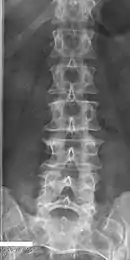

Lumbarization of sacral vertebra 1, seen as 6 vertebrae that do not connect to ribs.

Lumbarization is an anomaly in the spine. It is defined by the nonfusion of the first and second segments of the sacrum. The lumbar spine subsequently appears to have six vertebrae or segments, not five. This sixth lumbar vertebra is known as a transitional vertebra. Conversely the sacrum appears to have only four segments instead of its designated five segments. Lumbosacral transitional vertebrae consist of the process of the last lumbar vertebra fusing with the first sacral segment. [1] While only around 10 percent of adults have a spinal abnormality due to genetics, a sixth lumbar vertebra is one of the more common abnormalities. [2]